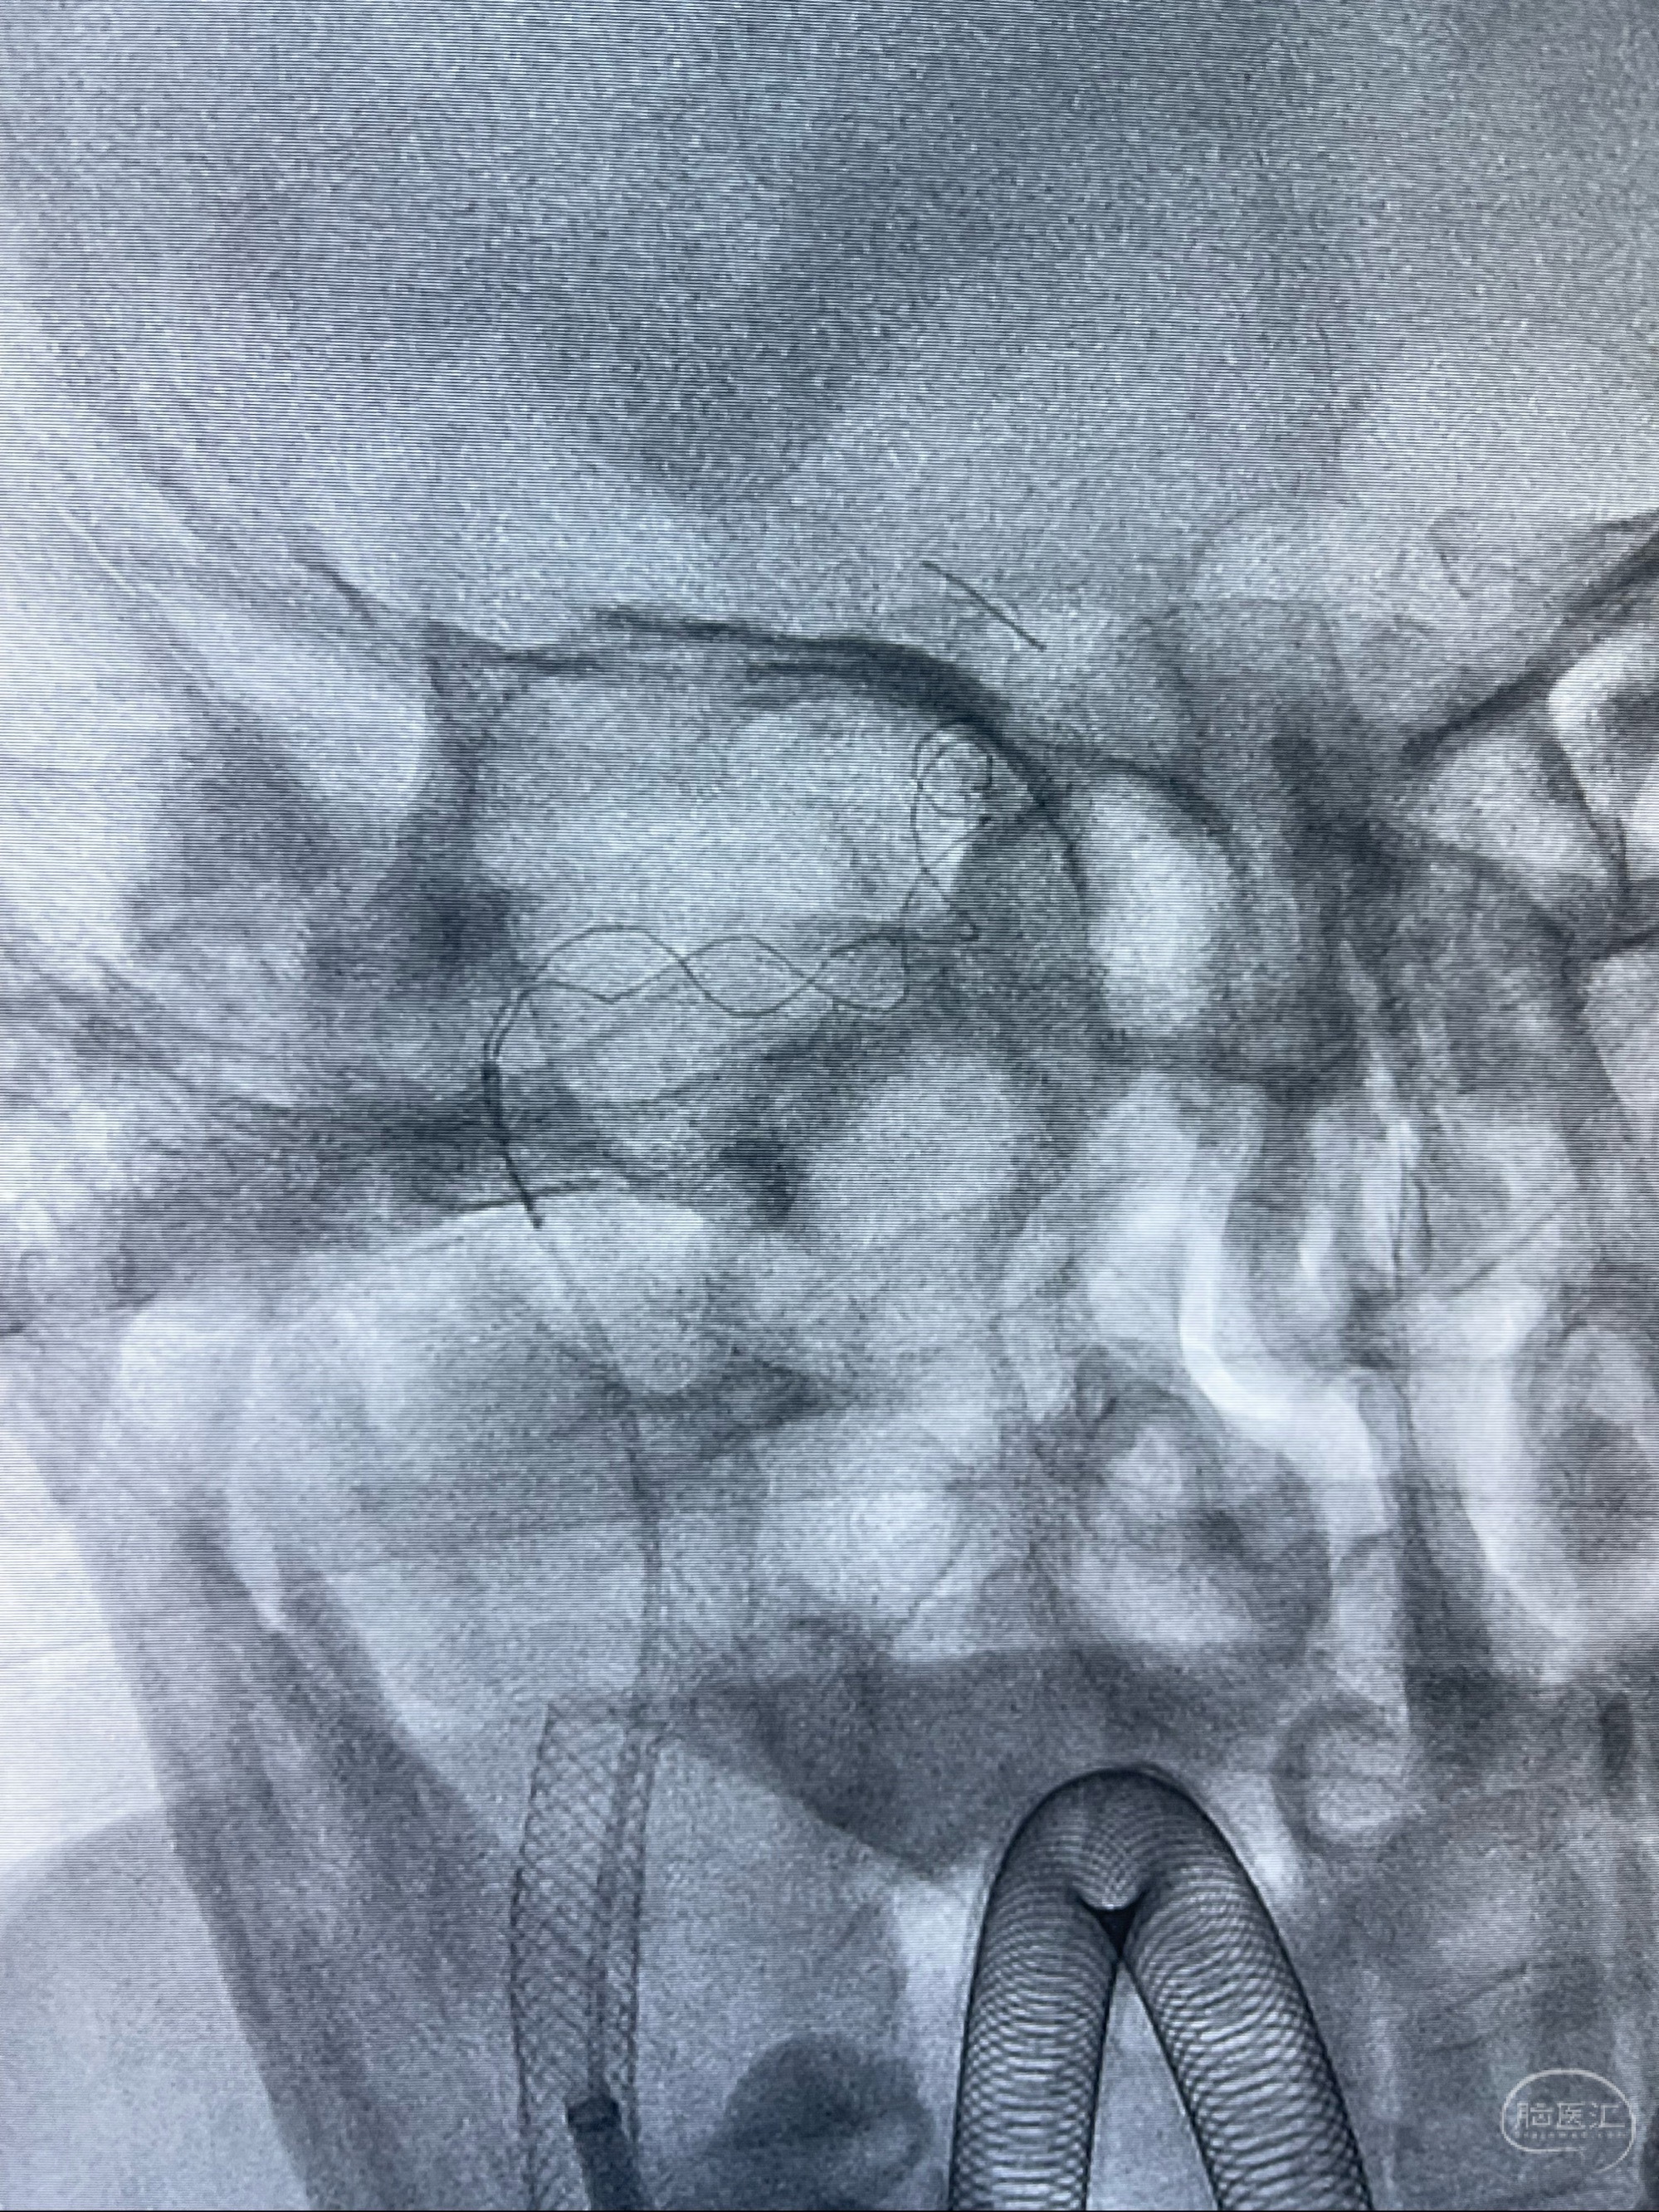

重新行“路径图”,支架导管在微导丝引导下超选择性插入至右侧颈内动脉眼段,4.5-50mmLeo支架释放,远心端位于海绵窦段,近心端位于岩骨段狭窄段以近

即刻造影显示支架贴壁佳

路径图下,5.5-50mmLeo支架导管在微导丝引导下超选择性插入远段Leo支架内

两枚支架部分重叠

多次确认支架位置及打开贴壁情况

支架完全打开,近心端位于原颈动脉支架远心端内

麻醉苏醒佳,遵嘱活动!

术后给予替罗非班300ug/h维持,序贯阿司匹林100mg➕泰嘉75mg口服